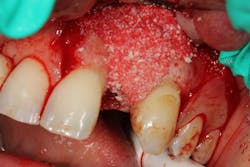

One particularly good bone graft material that provides scaffolding space maintenance as well as stabilizes the blood clot is Geistlich Bio-Oss Collagen (Geistlich Pharmaceuticals). (12) Geistlich Bio-Oss Collagen is 90% Bio-Oss granules (size range 0.25–1.0 mm) and 10% collagen. The proprietary formulation of the collagen component gives the material its scaffolding and moldability qualities, which makes it an excellent product for site preservation after tooth extraction, especially during flapless site preservation. (13) Finally, this graft material has been shown to outperform other graft materials in comparative studies looking at site preservation after tooth extraction. (14)

This surgical video demonstrates removal of a tooth with loss of buccal plate and grafting of the remaining socket with Geistlich Bio-Oss Collagen and Geistlich Bio-Gide to preserve the ridge for implant placement.